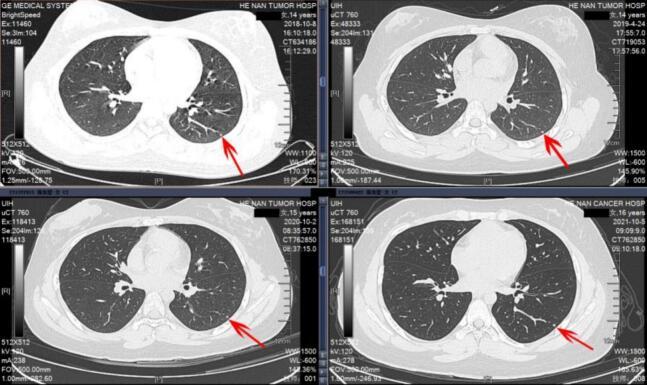

We retrospectively analyzed clinical data from 126 osteosarcoma patients aged 20 years or younger who were treated at Henan Cancer Hospital between January 2012 and January 2022. Pre-treatment thin-slice computed tomography (CT) scans of lung were used to categorize patients into three groups: no IPN (n = 100), solitary IPN (n = 16), and multiple IPNs (n = 10). Baseline characteristics, primary tumor parameters, treatment modalities, and follow-up data were collected. Univariate and multivariate analyses were conducted to assess risk factors and survival outcomes.

我们回顾性分析了2012年1月至2022年1月在河南省肿瘤医院接受治疗的126例20岁及以下骨肉瘤患者的临床资料。使用治疗前肺部薄层计算机断层扫描(CT)将患者分为三组:无IPN(n = 100)、孤立性IPN(n = 16)和多发性IPN(n = 10)。收集基线特征、原发肿瘤参数、治疗方式和随访数据。进行单因素和多因素分析以评估危险因素和生存结果。